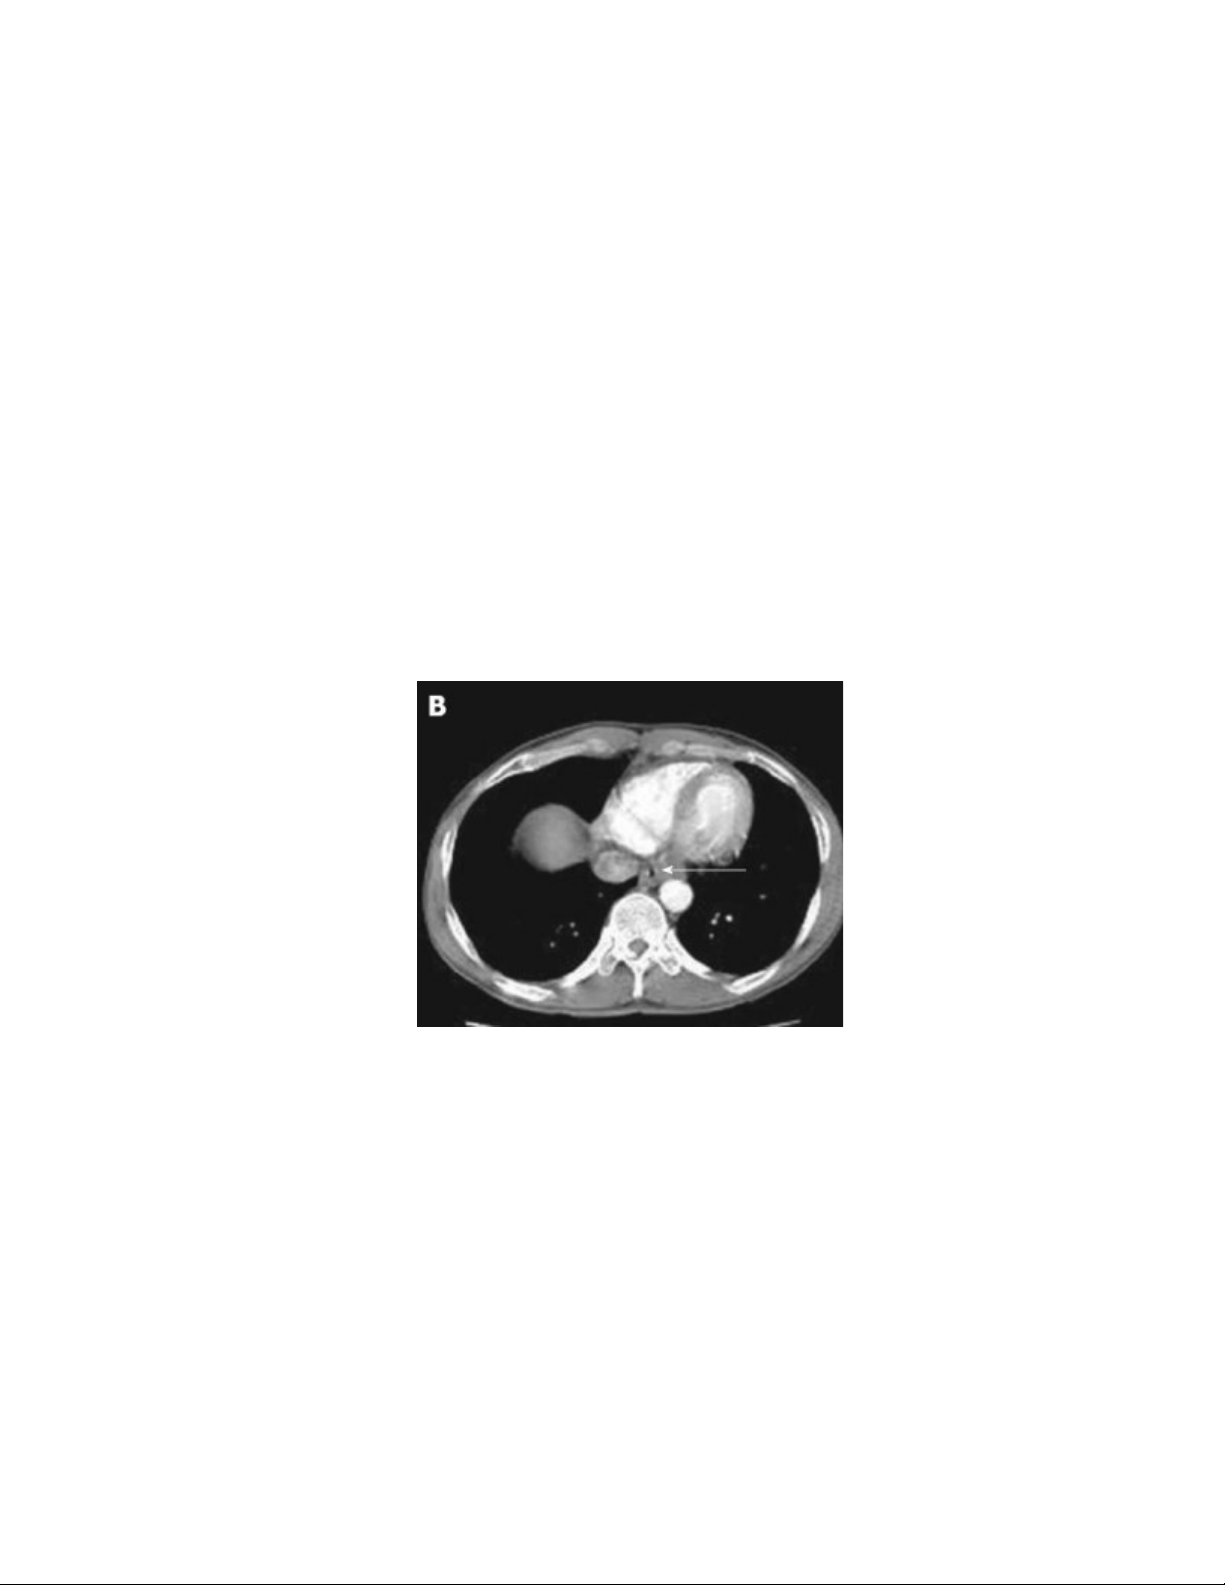

Chụp cắt lớp vi tính: cho thấy độ sâu của mô hoại tử, tình trạng mô lân cận và các

biến chứng của bỏng thực quản

Hình 5: Tổn thương thực quản trên cắt lớp vi tính